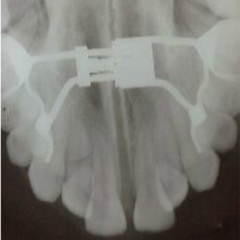

- We are discussing expansion. I am sure, we all have done few. We will revisit protocol.

- There are also other types of expanders besides RPE and we will look intot hem as well.

- Narrow maxilla is indicative of expansion in presense of a crossbite however, expansion is being used as a corrective treatment in Class II and Class III cases as well. We will examine latest literature on the subject.